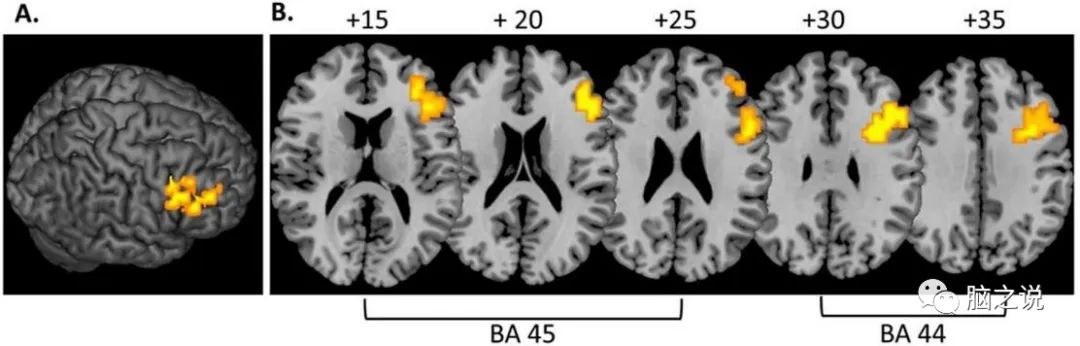

5.2.3子区功能连通性变化的统计分析

根据之前研究,以Brodmann 44区和Brodmann 45区的cluster为ROI (图2),进行了功能连接分析。首先研究者提取每个受试者整个ROI上的平均时间序列。然后将每个受试者的平均时间序列与全脑作相关,生成功能连接图,并转换到标准空间。通过确定每个体素的激活强度的中位数的相关系数来计算组间功能连接图。基于中位数的统计数据以便减少异常值的影响。

图2